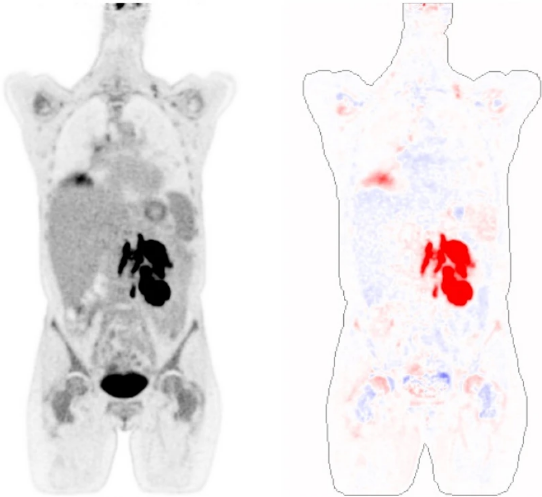

Normal twin PET: personalized generative modeling for confounder correction and anomaly detection in whole-body PET/CTChristian Hinge, Anders Bertil Rodell, Sven Zuehlsdorff, and 5 more authorsScientific Reports, Nov 2025Variable physiological [18F]FDG uptake patterns and a lack of labelled data make it challenging to automatically distinguish normal from pathological suspicious uptake in whole-body PET/CT imaging. We propose a deep learning method that generates patient-specific normal twin PET images to serve as personalized references for quantitative analysis and unsupervised detection of pathological anomalies. We developed an image-to-image generative model that synthesizes normal reference twin PET (ntPET) images from CT scans, patient demographics, and acquisition parameters. The model was trained on 2,538 pseudo-normal PET/CT studies, including stable lymphoma patients and manually disease-masked clinical scans. Model performance was evaluated on 177 test studies achieving 89.3% explained variance and 18.0% mean absolute relative error. We introduced a novel “twin correction” method which reduced SUVmean variance by up to 90% in various organs and successfully reduced confounding normally occurring effects of patient sex, age, fat mass, and uptake time. Finally, anomaly detection and unsupervised tumor segmentation was achieved by comparing actual PET scans with their normal twins. The ntPET-based method achieved a dice score of 49.3% on the AutoPET dataset without requiring tumor annotations for training. In conclusion, the proposed ntPET methodology employs personalized normal references to achieve disease-agnostic patient-specific analysis of PET images.